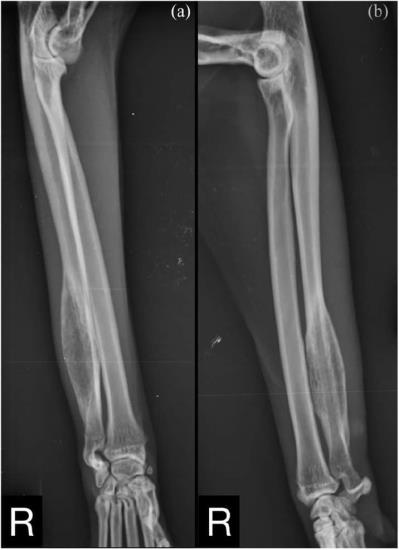

The diagnosis of cellulitis and osteomyelitis was made using. FEMORAL OSTEOMYELITIS AND OSTEOSARCOMA IN A DOG. This type of infection is referred to as osteomyelitis. We used to think a fungal infection was the better diagnosis of the. Enlarge Image Enlarge Image In this 8 yr old black female the best dx is.

The diagnosis of cellulitis and osteomyelitis was made using. Although the exact etiology is unknown there has been some evidence that derangement of bone growth or differentiation of new bone at the long bone metaphyses may be to blame. The tumour occurs more often in the front legs commonly affecting the bottom of the radius wrist joint or the top of the humerus. It most often develops in the large bones of the front radius and humerus and the large bones of the rear legs femur and tibia. FEMORAL OSTEOMYELITIS AND OSTEOSARCOMA IN A DOG.

FEMORAL OSTEOMYELITIS AND OSTEOSARCOMA IN A DOG. 0 Read Comments. Osteosarcoma in dogs is extremely aggressive. An increased alkaline phosphatase may be correlated with a poorer prognosis in cases of osteosarcoma. We were then told to see our regular vet on Monday.

Gold R Oliveira F Pool R. The vet thought Briggs could possibly have either osteosarcoma or osteomyelitis. This clinical report describes a 10-year-old female spayed German Shepherd dog cross that was presented with cellulitis of the left proximal forelimb and osteomyelitis of the left proximal humerus and was ultimately diagnosed with metastatic osteosarcoma. It most often develops in the large bones of the front radius and humerus and the large bones of the rear legs femur and tibia. It is important to get this seen by a veterinary professional right away because it is an extremely painful condition and could result in permanent damage to the bone or it can spread to other parts of the body.